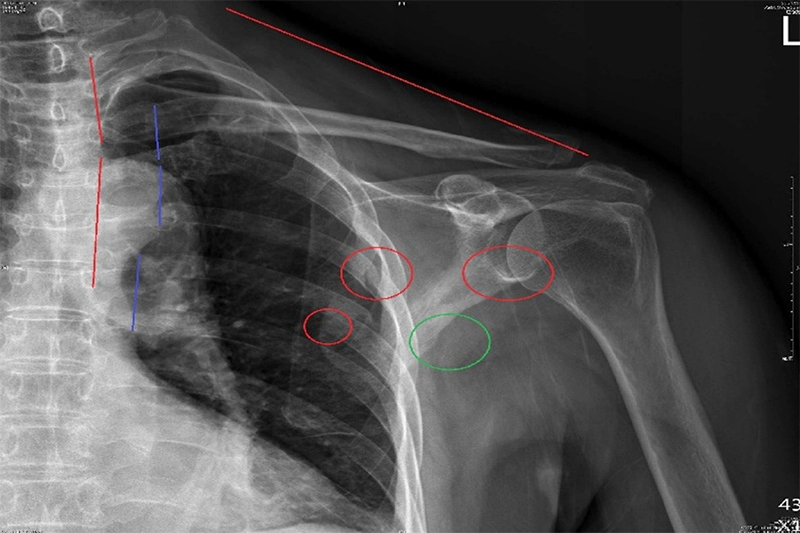

許多車禍患者在X光檢查後雖未顯示明顯骨折,但往往仍有持續的酸痛、頭暈、無力或姿勢歪斜等問題。彭偉嵐醫師指出:「這些症狀多半來自看不見的微細骨裂與深層內傷,若未即時矯正,常在數月後演變為慢性脊椎歪斜、骨盤傾斜或神經壓迫。」

針對這類隱性損傷,蘭陵中醫結合中醫經絡診斷與現代影像學評估,搭配由彭偉耘物理治療師所研發的「安全無創高階矯正手法」,能在不動刀、不麻醉的情況下,協助患者恢復脊椎排列與神經傳導。此療法已成功讓多名原本被建議開刀的患者重新站起,甚至重返工作與運動。